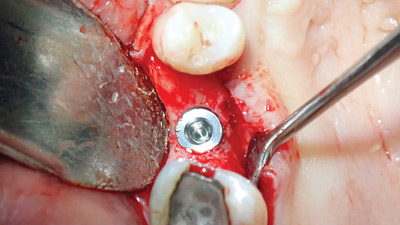

Osseodensification for Implant Dentistry: Multiple Clinical Applications

Osseodensification (OD) is a innovative technique that aims at bone preservation utilizing the collection of autogenous bone with nonsubtractive drilling within the implant site via the compaction of cancellous bone, which has good viscoelastic and plastic deformation characteristics. Unlike traditional osteotomy, OD does not excavate bone but simultaneously compacts and autografts the particulate bone in … Read more